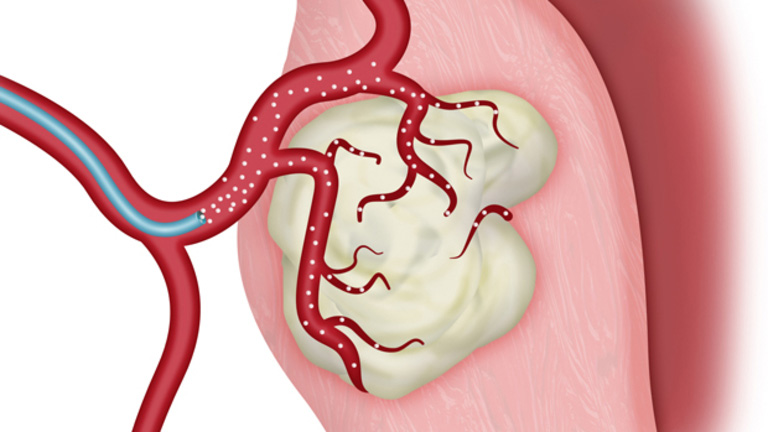

Phương pháp nút động mạch điều trị u xơ tử cung

Nút mạch là một thủ thuật ít xâm lấn, mới được nghiên cứu và ứng dụng trong ngành y tế gần đây. Phương pháp này sẽ hạn chế việc cung cấp máu cho khối u từ đó làm nó suy yếu. Hiện nay, nút mạch đang được áp dụng trong điều trị một số bệnh lý như: Ung thư gan, U xơ tử cung, U tuyến giáp…

Bệnh viện Bạch Mai đã nghiên cứu ứng dụng phương pháp này trong điều trị u xơ tử cung và kết quả đạt được khá khả quan.